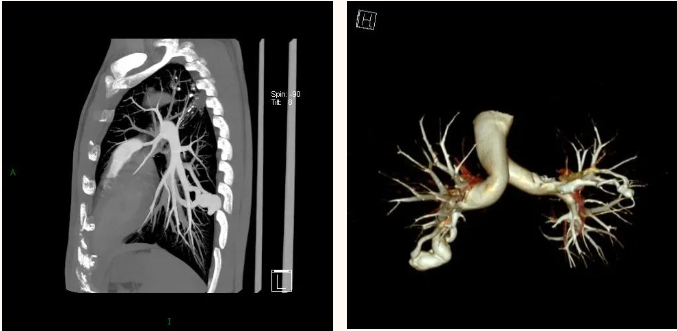

CT 血管造影(CTA),即 CT 血管成像,是一种利用计算机三维重建方法合成的非创伤性血管成像技术,可以在没有创伤的情况下,很好地了解身体中血管的情况。具有时间短、无创、特异性和敏感性高,时间和空间分辨率高等特点,能全方位显示出血管病灶,对于经其他检查已经明确患有血管疾病,需进一步了解病情严重程度具有重要的意义。

通过 CT 血管成像,可显示动脉病变,如血管闭塞、动脉瘤及夹层动脉瘤、血管畸形、血管损伤、心脏冠状动脉病变等。可进行冠心病 CT 筛查,冠心病术前、术后评估,脑卒中一站式检查,灌注成像等。

CT 血管造影(CTA)检查适用于动脉夹层、动脉瘤、不明原因出血、缺血性疾病、血管畸形、动脉栓塞、动脉硬化、动脉变异等血管疾病。

CTA 检查在大血管、外周血管疾病、心脏冠状动脉相关疾病、中枢神经系统疾病以及肿瘤疾病的诊断中发挥着重要作用。